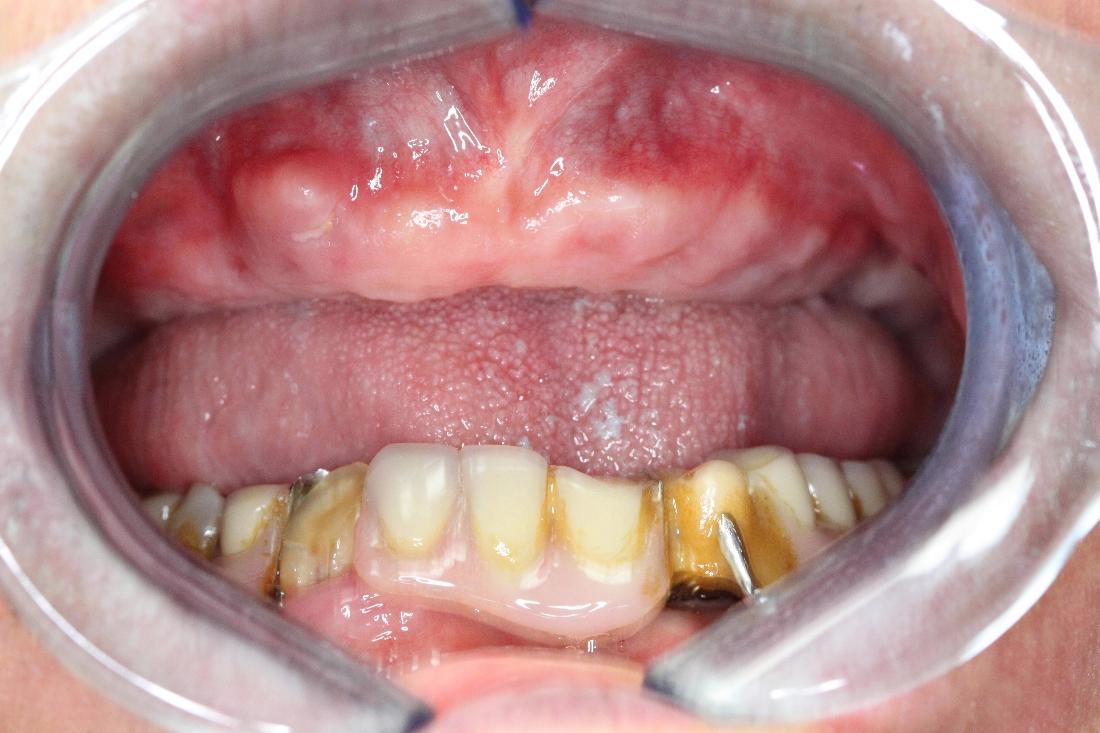

Upper Complete Denture

Patient presents to our office with infected and broken teeth. Patient decided to have extraction and wait to make new upper completed denture. Before picture shows completed removal of infection and broken teeth where tissue looks healthy with plenty amount of alveolar ridge. As a result, we are able to finish the case with a spectacular smile on our patient's face!